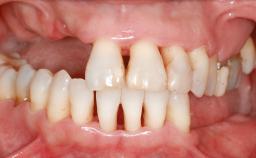

Ridge Preservation and Implant Placement for a Fixed Dental Prosthesis After a Car Accident

It is well known to clinicians that any removal of teeth will, over time, cause the dimensions of the alveolar ridge to be reduced by resorption of the bundle bone and by changes related to external modeling. This development is particularly evident in the crestal region with its thin buccal bone that consists of bundle bone almost entirely. The facial bone will rapidly resorb as blood supply from the periodontal ligament gets disrupted (Araújo and Lindhe 2005). There is no reason why traumatic tooth loss should not have the same consequences. It takes more than achieving implant osseointegration for a treatment outcome to be considered successful. No deficiency of bone or soft tissue is acceptable when an ideal esthetic outcome is the goal. Several articles (Sanz and coworkers 2011; Vignoletti and coworkers 2011) have reported on techniques of improving the alveolar ridge for implant treatment, notably focusing on protecting tissues from resorption.